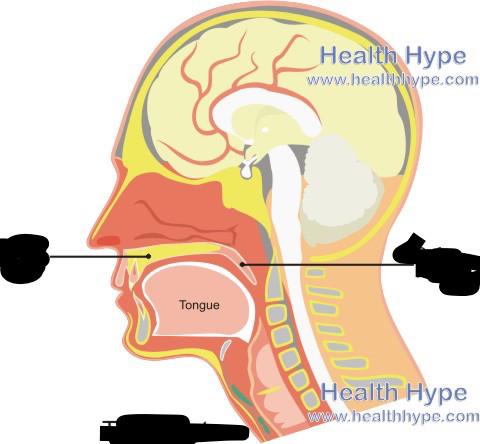

Hard/soft palate

Inferior/middle/superior concha (s.) conchae (pl.)

Nares

Nasal Cavity

Nasal septum

Naso/oro/laryngo-phraynx

Oral Cavity

Tongue

Uvula

Vestibule (of nasal cavity)

Vocal folds (=vocal cords)